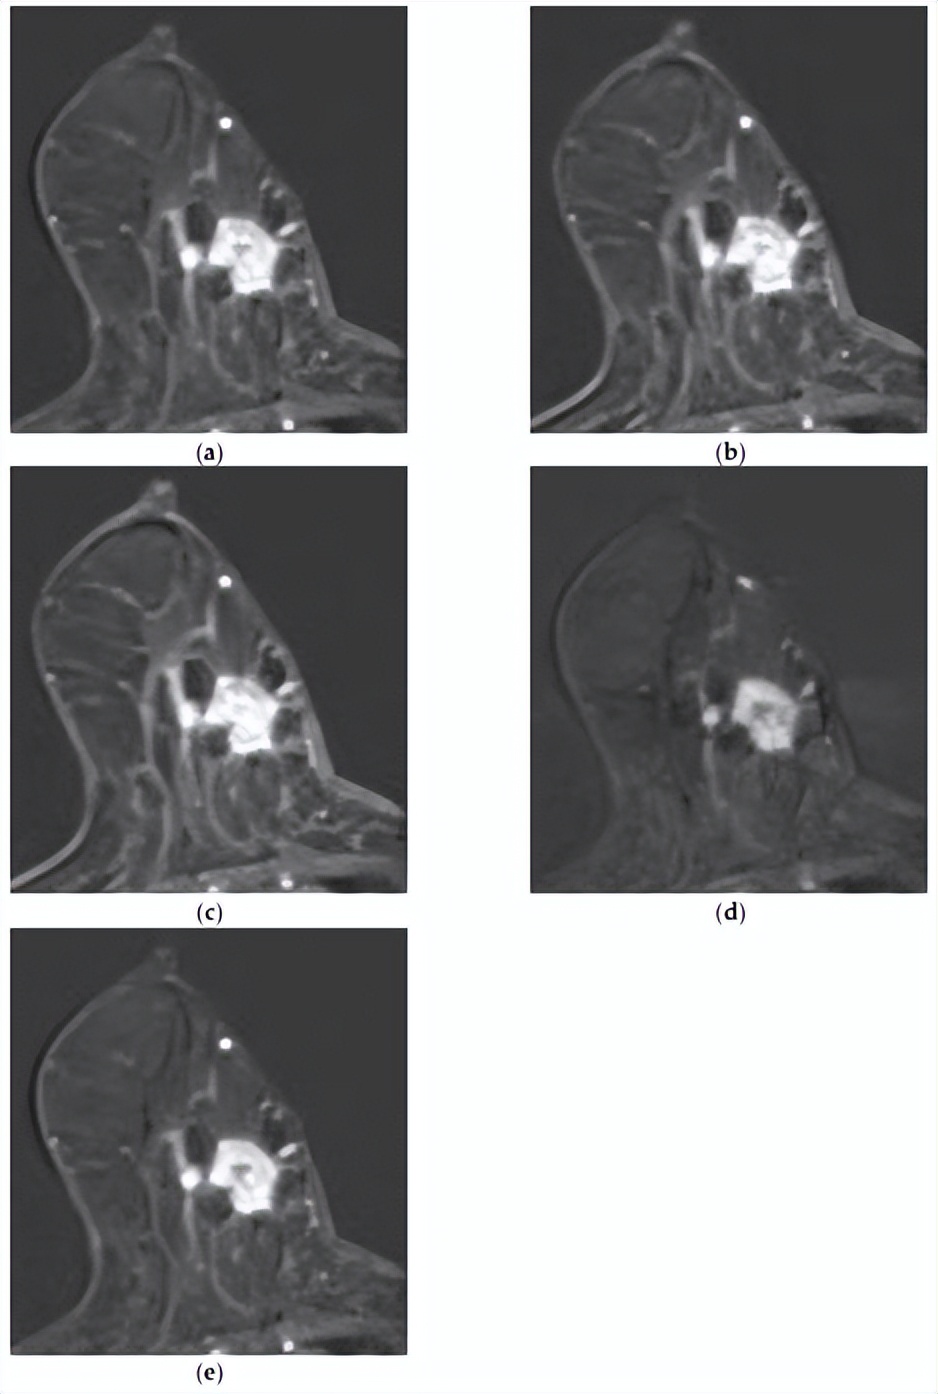

[MRI和组合模型均正确预测了复发。一名50岁女性,具有不均匀致密的纤维腺体组织和中度背景实质强化。注射对比剂后(a)1分钟、(b)2分钟、(c)3分钟、(d)4分钟和(e)5分钟的轴向增强T1加权MR图像显示,左乳房12点位置有一个1.8×1.6厘米的不规则形状、边缘有毛刺、边缘增强的肿块。在主要病变后方可见另一个8毫米增强肿块,侧面还有另外两个8毫米增强肿块,它们似乎相互连接。虽然图像中未显示,但上内象限存在另一个增强病变,证实了多中心疾病。两种模型均成功预测了该复发病例。]